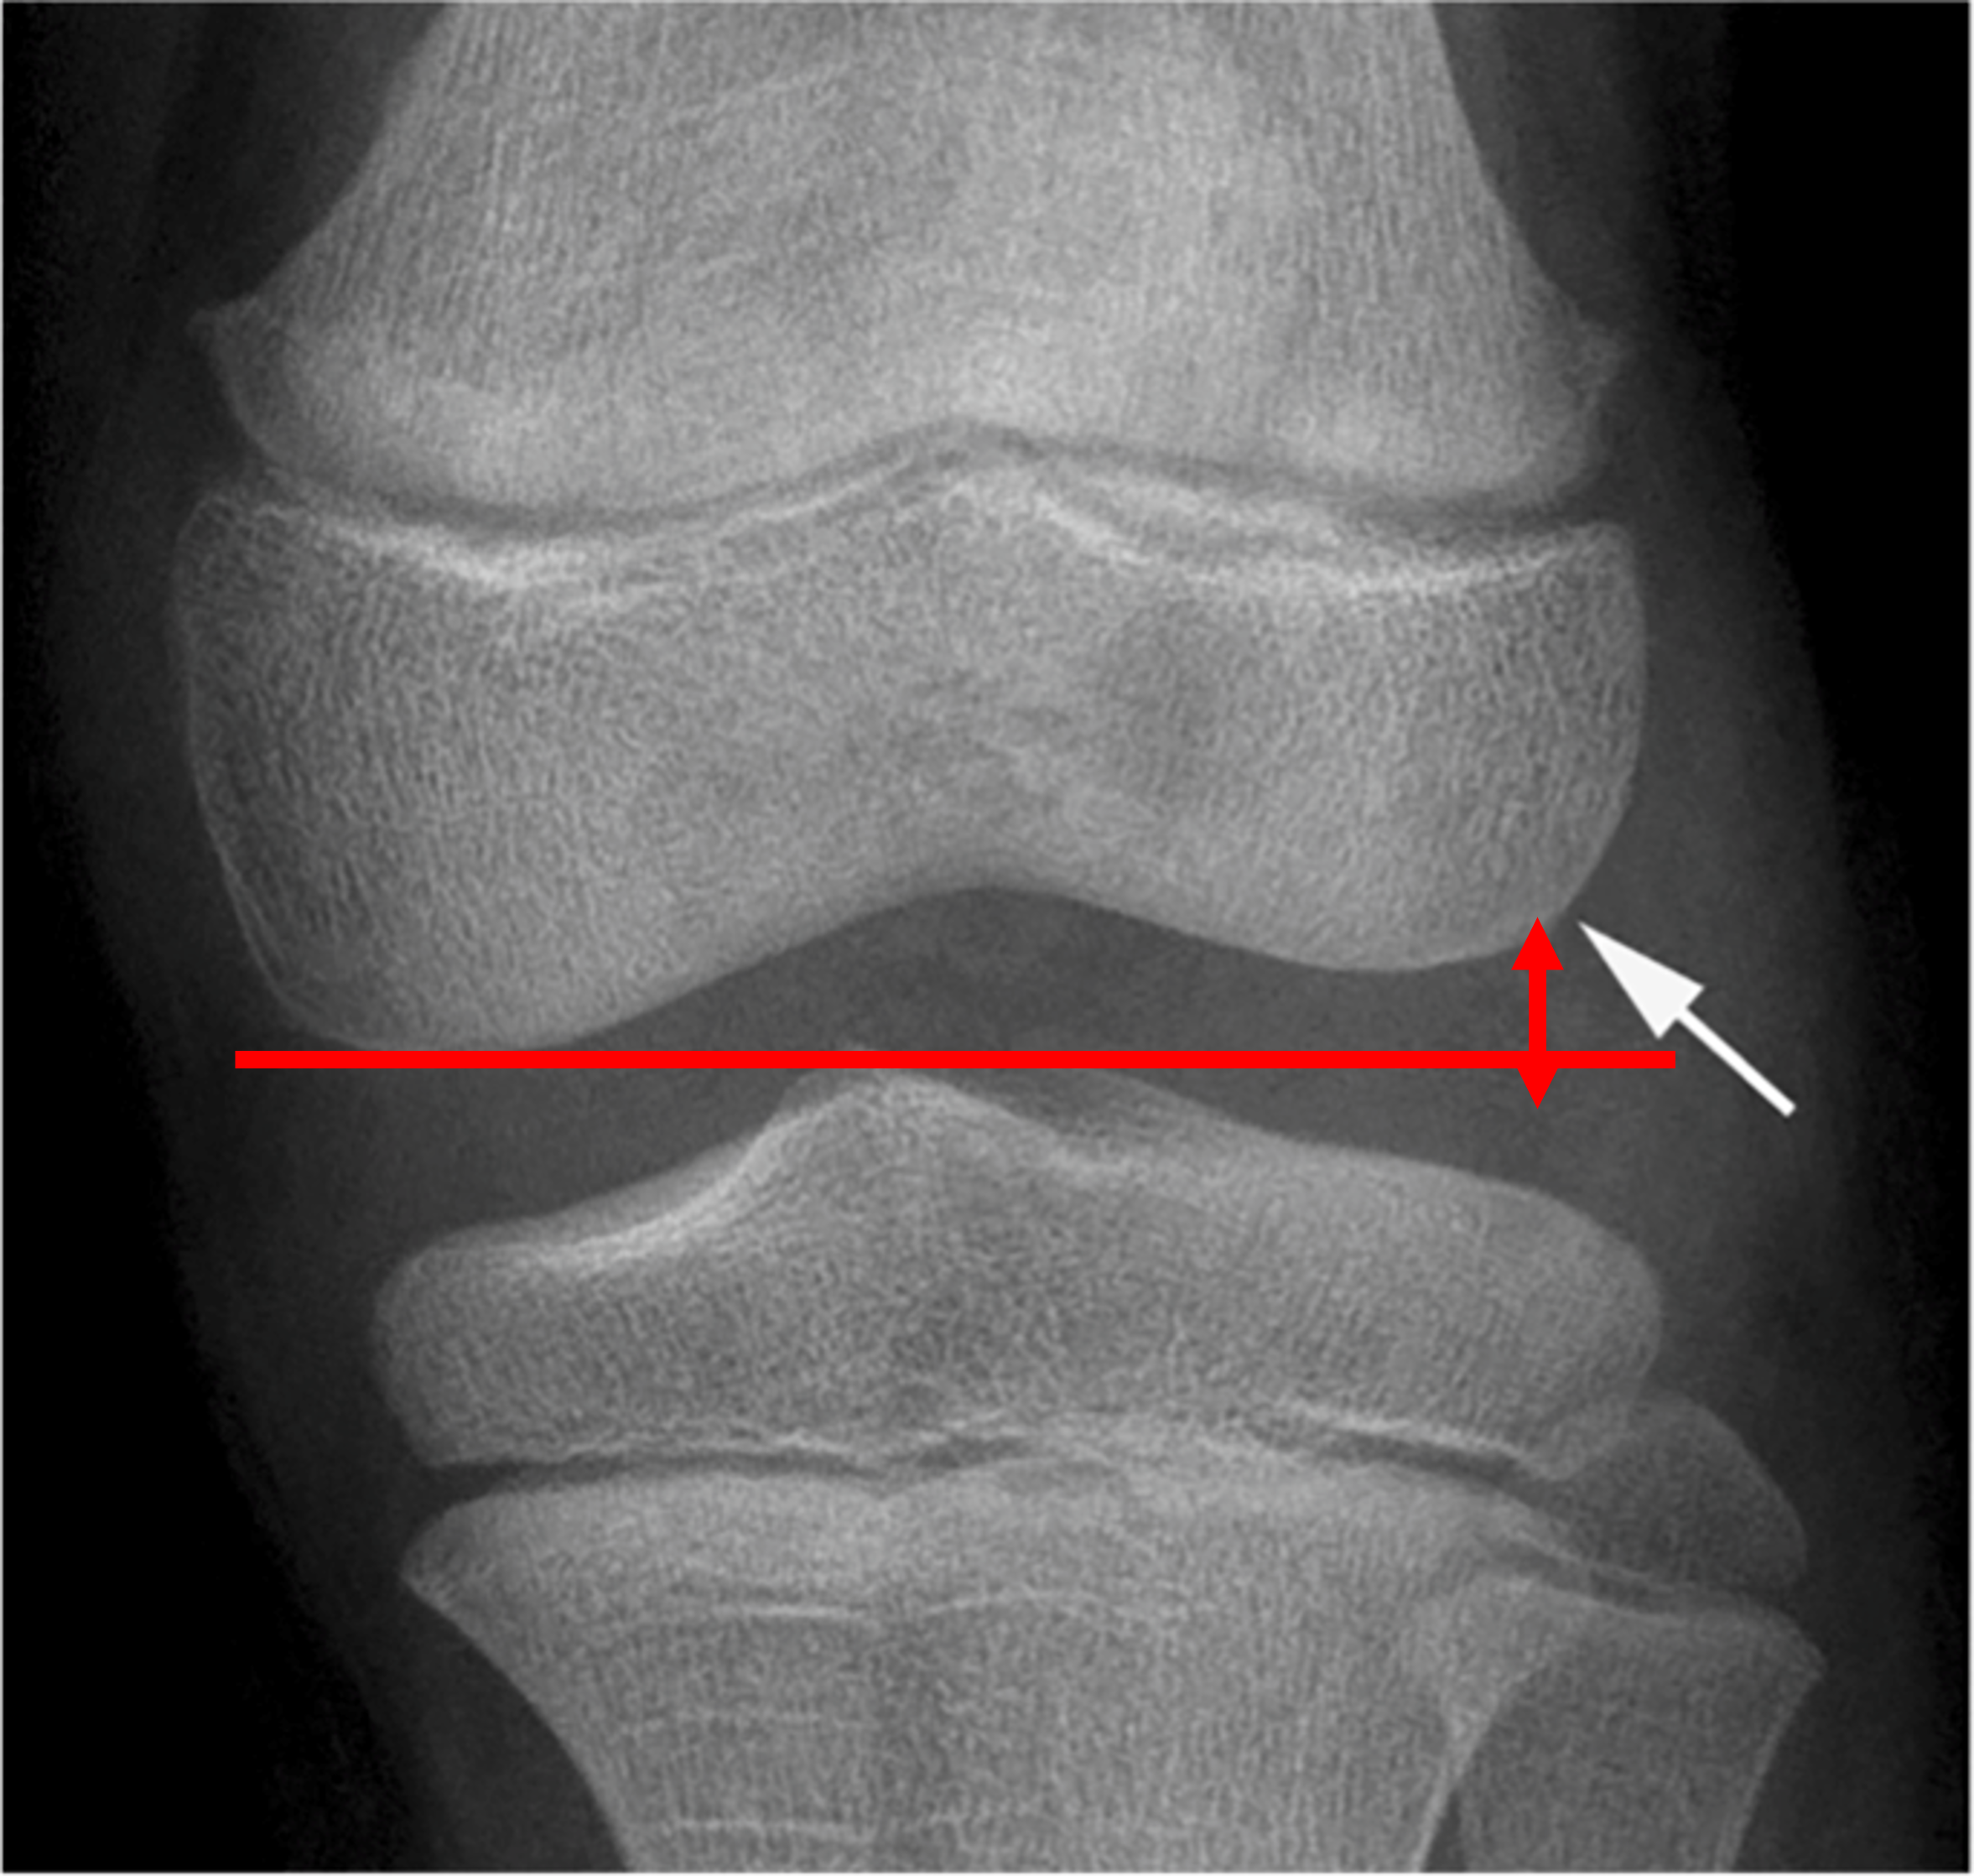

마지막으로 가장 중요한 증상은, "압통"입니다. 압통이란, 환부를 눌렀을 때 통증을 호소하는 것을 말합니다. 반월상 연골은 콜라겐 섬유로 이루어져 있기 때문에, 신경 가지가 안까지 뻗어있지 못합니다. 따라서, 설사 찢어졌다고 하더라도, 그것을 감지할 수 있는 신경 자체가 반월상 연골에는 없기 때문에, 간접적으로 반월상 연골 주변의 관절낭 등의 염증을 촉지함으로써 감지할 수 밖에 없습니다. 이때 주로 압통이 발생하는 지역은, 위 사진에 표시한 곳으로, 반월상 연골이 파열될 경우 염증 물질이 해부학적으로 모일 수 밖에 없는 위치에 해당합니다.

반월상 연골 질환에서 X-ray는 반월상 연골이 쉽게 찢어질 수 있는 질환인 원판형 반월상 연골 (추후 링크 추가 예정.) 등을 감별하는데 도움을 줄 수 있습니다. 원판형 반월상 연골은 반월상 연골을 구성하는 콜라겐 섬유의 조성이 일반 반월상 연골과 달라 내구성이 떨어지고, 특징적으로 반월상 연골이 무릎 관절 중앙부로 갈수록 얇아져야하지만 두께가 유지되는 모양으로인해 X-ray상 대퇴골선 정상적인 환자와 비교하였을 때 올라가있고 비교적 평평한것을 볼 수 있습니다.